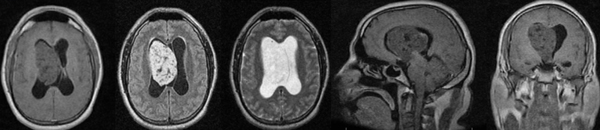

Un hombre de 45 años de edad con antecedentes de asma, consultó al servicio de urgencias por cefalea holocraneana de intensidad 9/10 en la escala numérica análoga, de tipo opresiva que mejoraba parcialmente con analgésicos, asociada a alteración en la marcha. Al examen físico neurológico presentaba una paresia leve en el miembro inferior derecho. Se realizó una resonancia magnética (RM) de cerebro la cual evidenció una gran lesión a nivel del cuerpo del ventrículo lateral derecho de 7 x 6 x 7 cm que sobrepasaba la línea media y se extendía al III ventrículo. Tras la administración de contraste se evidenció un leve realce heterogéneo. Así mismo se evidenció una leve dilatación ventricular (Figura 1).

Figura 1: resonancia magnética de cerebro que evidencia una lesión heterogénea a nivel del ventrículo lateral derecho con extensión al III ventrículo y desplazamiento de línea media, la cual realza luego la administración de contraste.